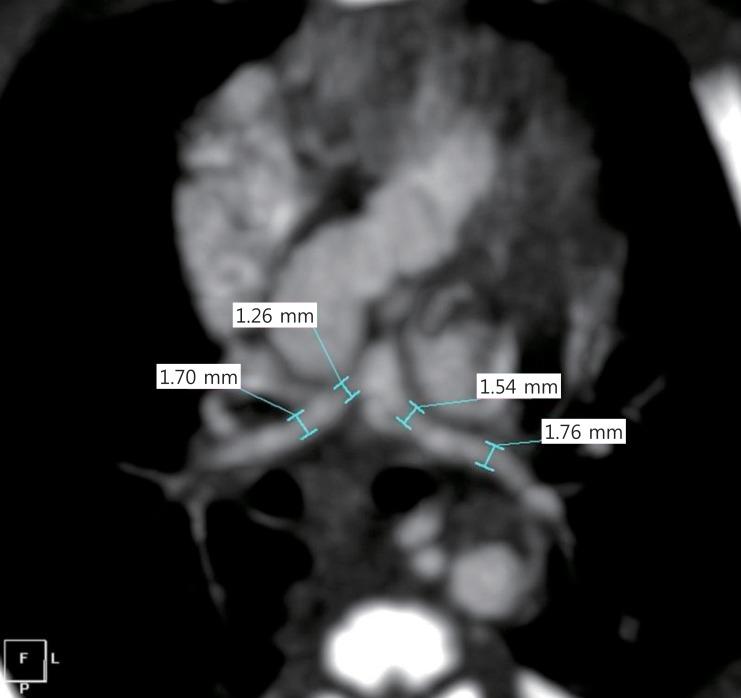

Recently, surgical outcomes of repair of tetralogy of Fallot (TOF) have improved. For patients with TOF older than 3 months, primary repair has been advocated regardless of symptoms. However, a surgical approach to symptomatic TOF in neonates or very young infants remains elusive. Traditionally, there have been two surgical options for these patients: primary repair versus an initial aortopulmonary shunt followed by repair. Early primary repair provides several advantages, including avoidance of shunt-related complications, early relief of hypoxia, promotion of normal lung development, avoidance of ventricular hypertrophy and fibrosis, and psychological comfort to the family. Because of advances in cardiopulmonary bypass techniques and accumulated experience in neonatal cardiac surgery, primary repair in neonates with TOF has been performed with excellent early outcomes (early mortality<5%), which may be superior to the outcomes of aortopulmonary shunting. A remaining question regarding surgical options is whether shunts can preserve the pulmonary valve annulus for TOF neonates with pulmonary stenosis. Symptomatic neonates and older infants have different anatomies of right ventricular outflow tract (RVOT) obstructions, which in neonates are nearly always caused by a hypoplastic pulmonary valve annulus instead of infundibular obstruction. Therefore, a shunt is less likely to preserve the pulmonary valve annulus than is primary repair. Primary repair of TOF can be performed safely in most symptomatic neonates. Patients who have had primary repair should be closely followed up to evaluate the RVOT pathology and right ventricular function.

最近,法洛四联症(TOF)修复手术的效果有所改善。对于年龄大于3个月的TOF患者,无论有无症状,均提倡一期修复。然而,对于新生儿或极小婴儿期有症状的TOF,其手术方法仍不明确。传统上,这类患者有两种手术选择:一期修复与先行体肺分流术随后再进行修复。早期一期修复有诸多优点,包括避免分流相关并发症、早期缓解缺氧、促进肺正常发育、避免心室肥厚和纤维化以及给家庭带来心理安慰。由于体外循环技术的进步以及新生儿心脏手术经验的积累,TOF新生儿的一期修复取得了良好的早期效果(早期死亡率<5%),这可能优于体肺分流术的效果。关于手术选择,一个尚存的问题是分流术能否为有肺动脉狭窄的TOF新生儿保留肺动脉瓣环。有症状的新生儿和较大婴儿的右心室流出道(RVOT)梗阻解剖结构不同,新生儿几乎总是由肺动脉瓣环发育不良而非漏斗部梗阻引起。因此,分流术相比一期修复更不太可能保留肺动脉瓣环。大多数有症状的新生儿可以安全地进行TOF一期修复。接受一期修复的患者应密切随访,以评估RVOT病理情况和右心室功能。